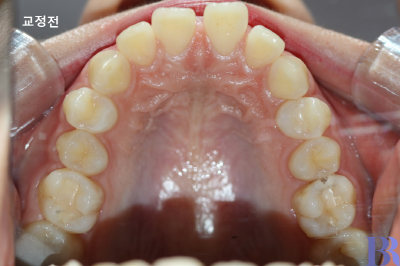

위에 사진은 교정 전후

윗니 모습을 비교한 것인데,

상악 제1 작은어금니가

발치된 것을 볼 수 있습니다.